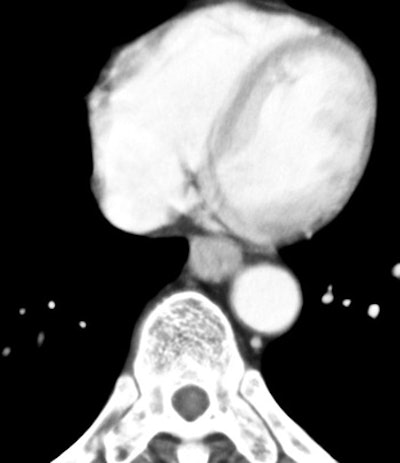

![]() |

| Venous-phase image of 64-year-old male with T3 esophageal cancer. On this phase, the tumor can be seen as well. |